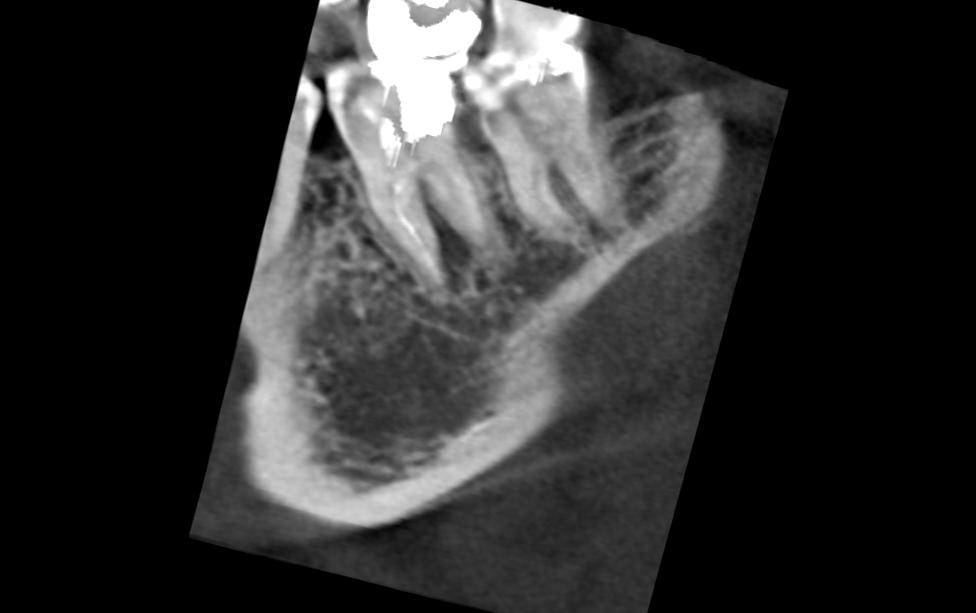

А вот такие снимки чтото скажут:Нажмите на изображение для увеличения

Название: Image1.jpg

Просмотров: 73

Размер:	14.4 Кб

ID:	4314305Нажмите на изображение для увеличения

Ну в чем же вода - все сходятся на том, что надо удалять. Не затягивая, т.к свищ по проекции межкорневой гранулемы и грануляции сособсвуют разрушению кости, чем дальше, тем больше... И потом тяжело будет имплант ставить... Куда уж конкретнее?!?

Проблема в том, что даже идеальная перепломбировка каналов гранулему не уберет, а при попытке оперативно убрать гранулему, убрать всю пломбу чтобы получить доступ к каналам и перелечить каналы, пройдя по изогнутым каналам мимо заломанного инструмента, от зуба ничего не останется.... "выкрасить и выбросить"...